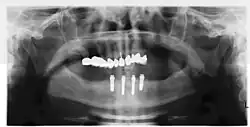

Implant retained fixed bridge or implant supported bridge

An implant supported bridge (or fixed denture) is a group of teeth secured to dental implants so the prosthetic cannot be removed by the user. They are similar to conventional bridges, except that the prosthesis is supported and retained by one or more implants instead of natural teeth. Bridges typically connect to more than one implant and may also connect to teeth as anchor points. Typically the number of teeth will outnumber the anchor points with the teeth that are directly over the implants referred to as abutments and those between abutments referred to as pontics. Implant supported bridges attach to implant abutments in the same way as a single tooth implant replacement. A fixed bridge may replace as few as two teeth (also known as a fixed partial denture) and may extend to replace an entire arch of teeth (also known as a fixed full denture). In both cases, the prosthesis is said to be fixed because it cannot be removed by the denture wearer.[14]